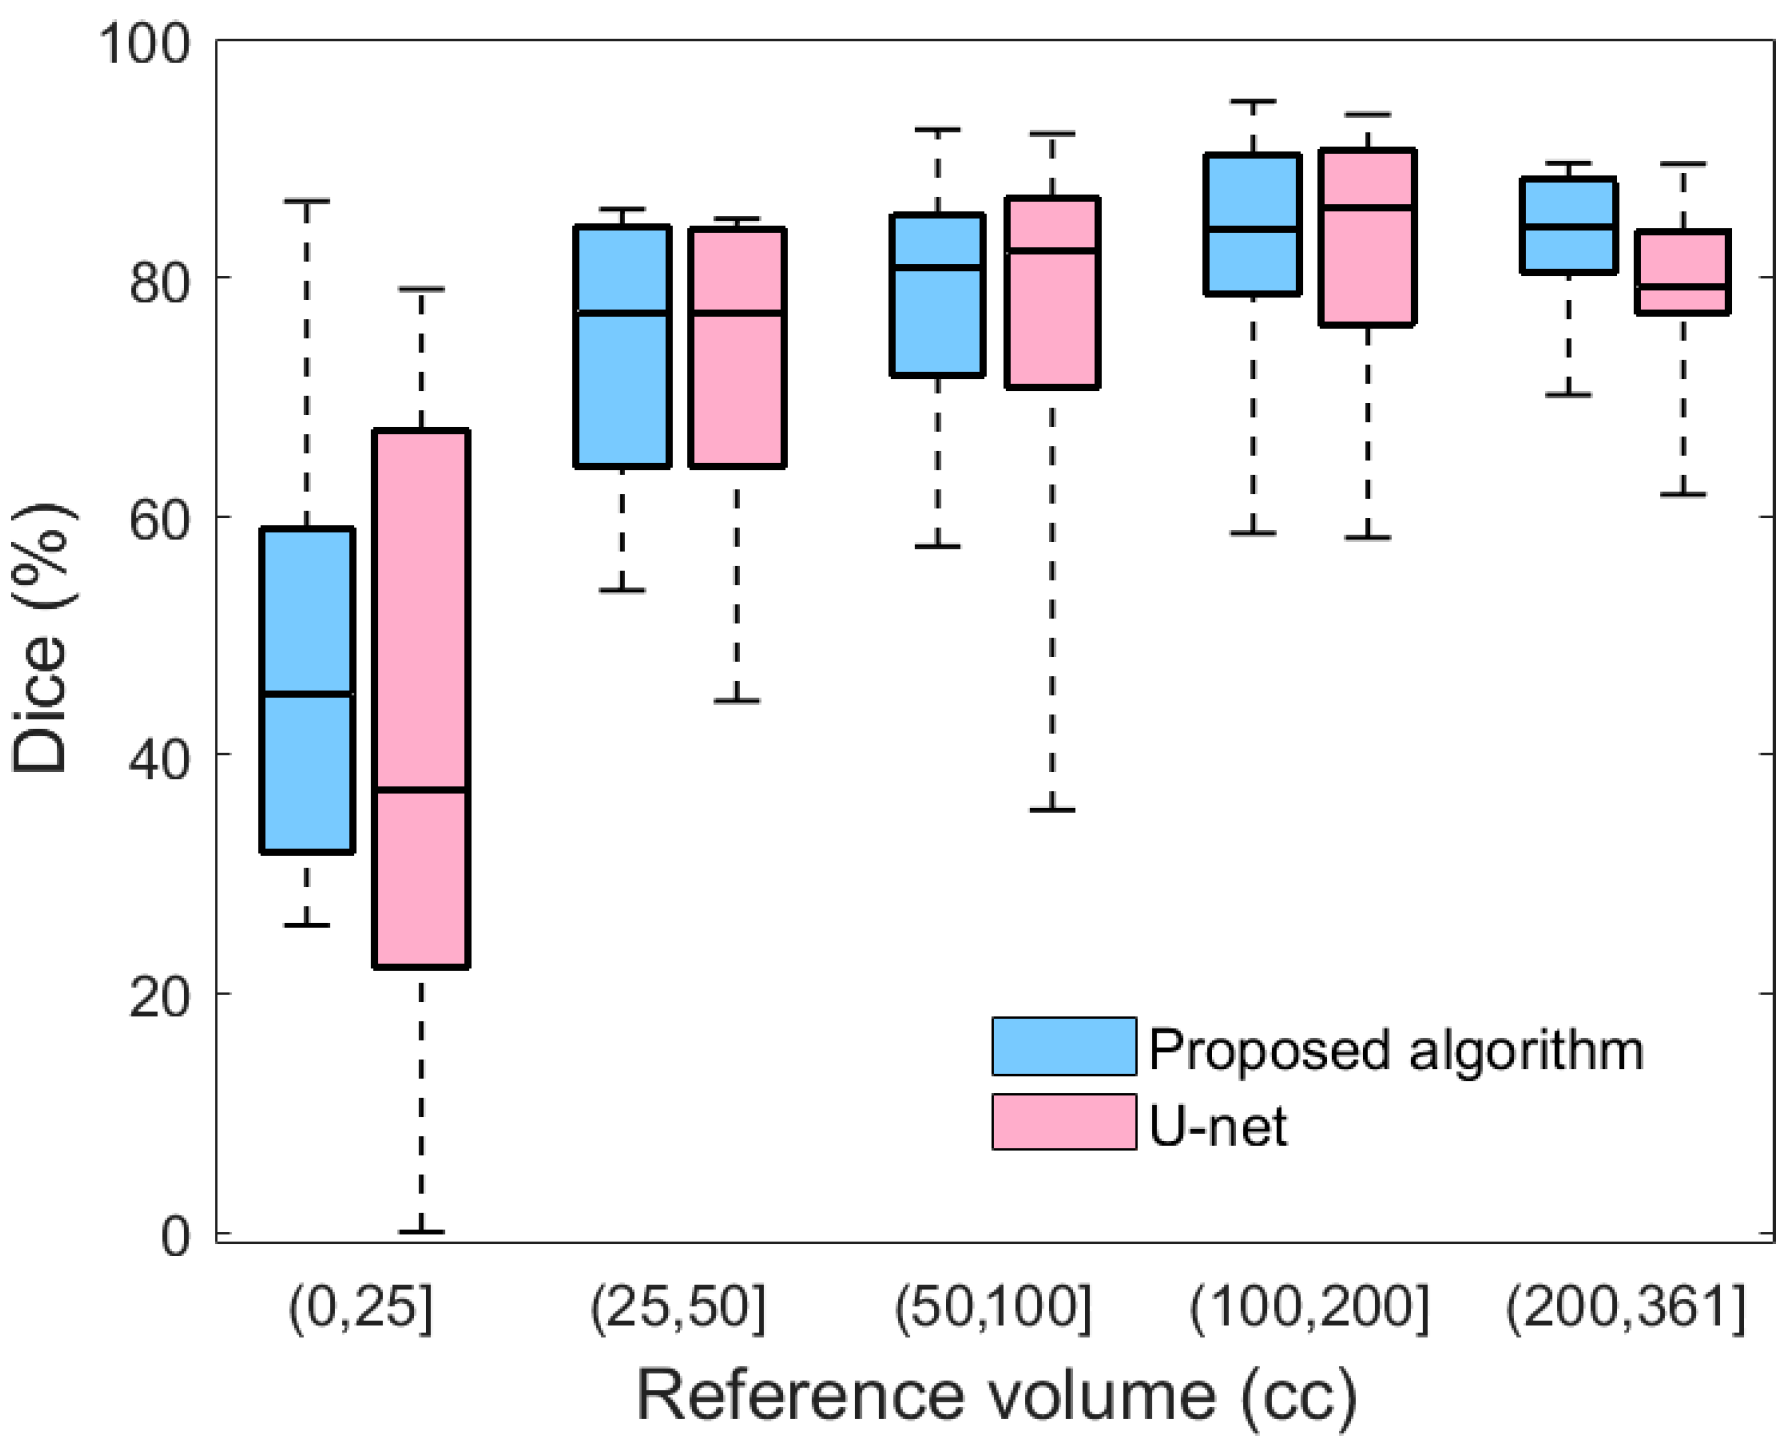

Table 1 also provides a comparison between the performance of the proposed method and the U-net model. To ensure a fair comparison, both models were trained using 10-fold cross-validation. As shown in

Table 1, the proposed method outperforms U-net in terms of both the average Dice value and the standard error of the mean. Moreover, the summary statistics in

Figure 9 evidence that compared to U-net, the proposed method yields less variability for all severity levels. Likewise, the lower extreme of the proposed method is greater than the lower extreme of U-net in all categories. In particular, for mild hematomas with less than 25 cc of blood, more than 25% of U-net’s Dice values are lower than any of those from the proposed method. The lower average performance and higher variability of U-net may be because deep learning approaches require a large and representative sample of annotated images. Thus, a deep learning model trained on limited datasets may fail to reflect the unseen spectrum of the real-world data distribution. Integrating hand-crafted features that reflect human domain knowledge can compensate for this limitation of deep models, yielding segmentation results that are more consistent and robust.

Figure 9.

A box plot comparing the Dice similarity coefficients of the proposed algorithm and U-net with respect to the severity of hematoma.

Figure 9.

A box plot comparing the Dice similarity coefficients of the proposed algorithm and U-net with respect to the severity of hematoma.